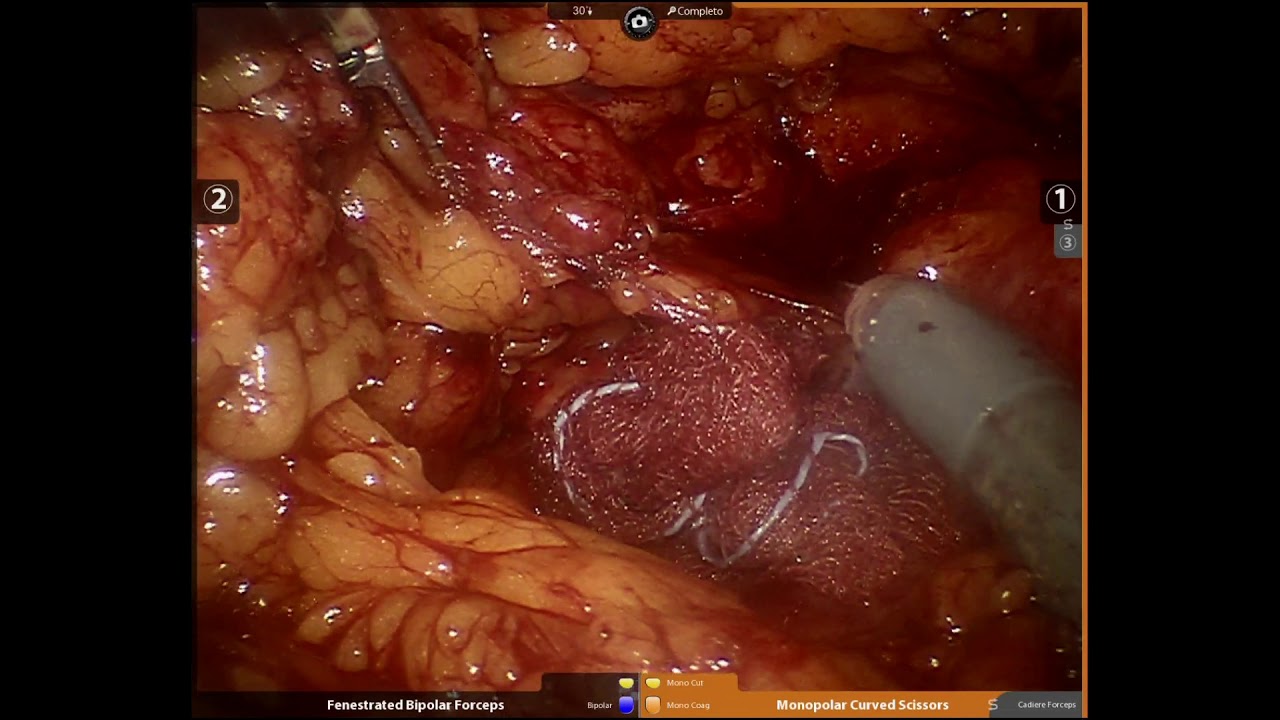

Fotos e vídeos